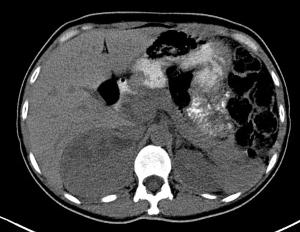

(2)CT 是目前首选的定位检查手段。嗜铬细胞瘤在CT上多表现为类圆形肿块,密度不均匀,出血区或钙化灶呈高密度,增强扫描时肿瘤实质明显强化,而坏死区无或略有强化。CT诊断肾上腺内嗜铬细胞瘤的敏感性达到93%~100%,但特异性不高,只有70%。对于肾上腺外嗜铬细胞瘤,如腹腔内小而分散的肿瘤不易与肠腔的断面相区分,因此有可能漏诊。